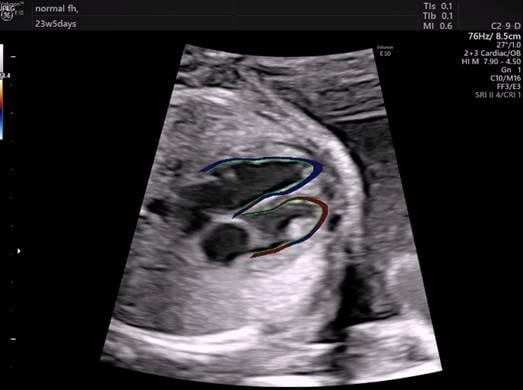

November 7, 2019 — A new imaging technique to track maternal blood flow to the placenta has the potential to help ...